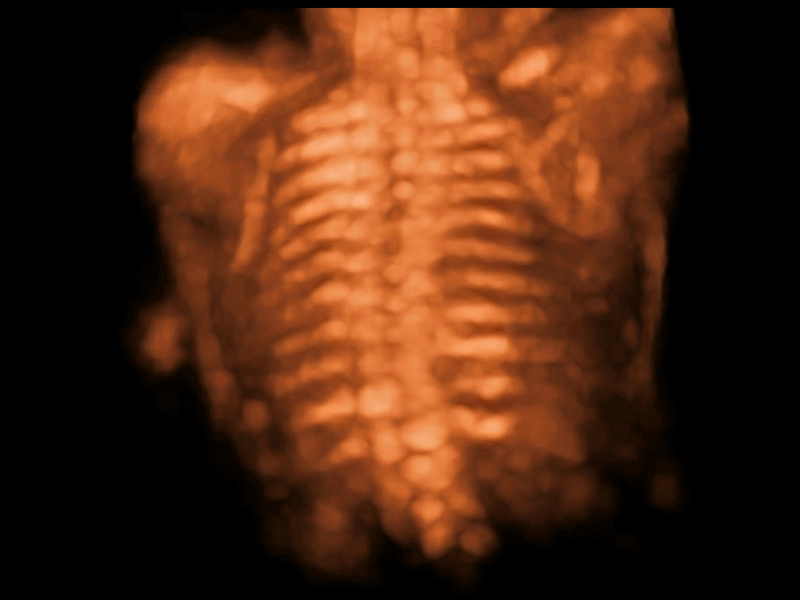

S-Fetus基于大数据深度学习算法,能够帮助您在产前筛查过程中智能识别胎儿标准切面、自动测量并录入报告。一个按键,即可智能、精准、高效地获取胎儿生理指标,极大简化您的产科检查操作。

可快速对产科扫查切面完成胎儿生理学参数的自动测量,减少操作者按键次数,大幅提升检查效率。

自动识别颈项透明层并获得NT值,为早孕胎儿畸形筛查提供有效测量工具,提高诊断效率和诊断信心。